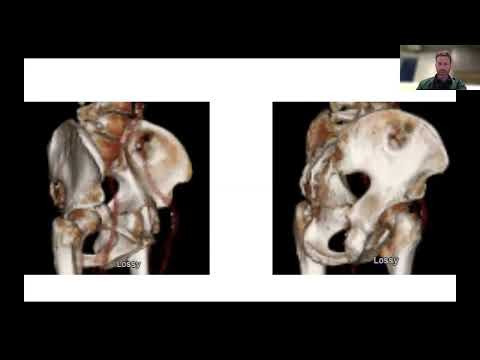

Pelvis is an approved indication in the US. For more detailed procedural information including Indications, Warnings, Cautions, Risks & Contraindications, visit illuminoss.com.